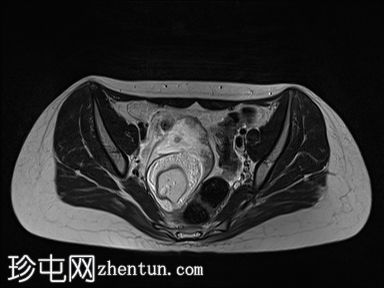

MRI扫描

轴向扫描

T2

右侧附件区可见较大囊性肿块,内含脂肪和液体,大小约为86毫米 x 60毫米。右侧血管蒂扭转,呈漩涡征。右侧卵巢可见增大充血的卵泡,为囊性肿块病变。左侧卵巢正常。